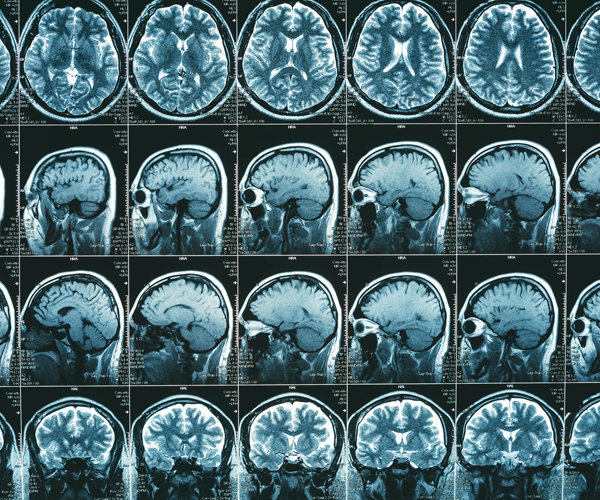

Many brain injury deaths could be prevented by using an inexpensive drug in the critical hours following a head trauma, a new international study finds.

For the study, researchers assessed the use of tranexamic acid (TXA), which prevents bleeding into the brain by inhibiting blood clot breakdown, in traumatic brain injury patients.

The 12,000 patients at 175 hospitals in 29 countries received either intravenous TXA or an inactive placebo.

Treatment with TXA within three hours of brain injury reduced the risk of death, the investigators found. The benefits were greatest in patients with mild and moderate brain injury (20% reduction in deaths), while there was no clear survival benefit seen in patients with the most severe brain injuries.

In addition, there was no evidence of harmful side effects and no increase in disability in survivors who received TXA, according to the study.

Traumatic brain injury is a leading cause of death and disability worldwide, with an estimated 69 million new cases each year, the study authors noted.

While TXA can prevent brain bleeding from getting worse, it can’t repair damage already done, so early treatment is critical. There was a 10% reduction in effectiveness for every 20-minute delay, the researchers found.